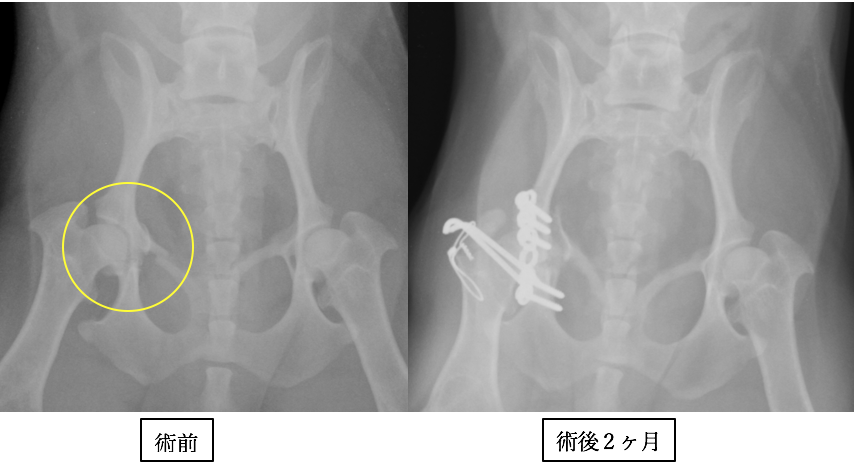

ポメラニアンの骨盤骨折です。両側であり、手術時間の短縮と固定力の強化のためにロッキングプレート・スクリュー(プレートとスクリューが固定されるシステム)を使用しました。プレート抜去はしなくても良いタイプです。